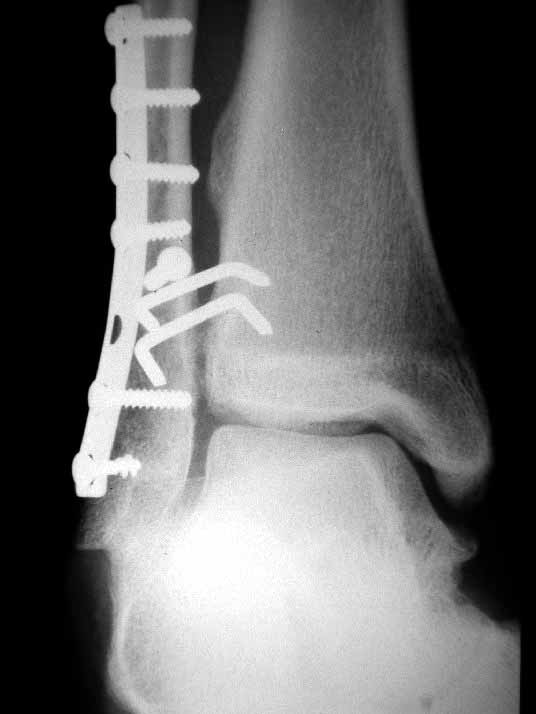

I would approach this problem by exposing medial, and reducing the talus to the medial side- hold it with a pin. I would then address lateral, and do whatever it took to reposition the fibula as others have stated so well. My personal preference for syndesmosis reconstruction is two medium barbed staples that parallel the ant tib-fib ligament (referenced in Kelikian's book on the ankle) +/- a ligament weave to try and reconstitute the tib-fib ligament. The staples stay in for good, and are more reliable than screws in my anecdotal experience. See attachments below. Patient presented after 3 attempts to squeeze the mortise down. Fibular shortening and malrotation present. Rx with lengthening and derotation + staple fixation of the syndesmosis.

James B. Carr, MD

Palmetto Health Orthopedics